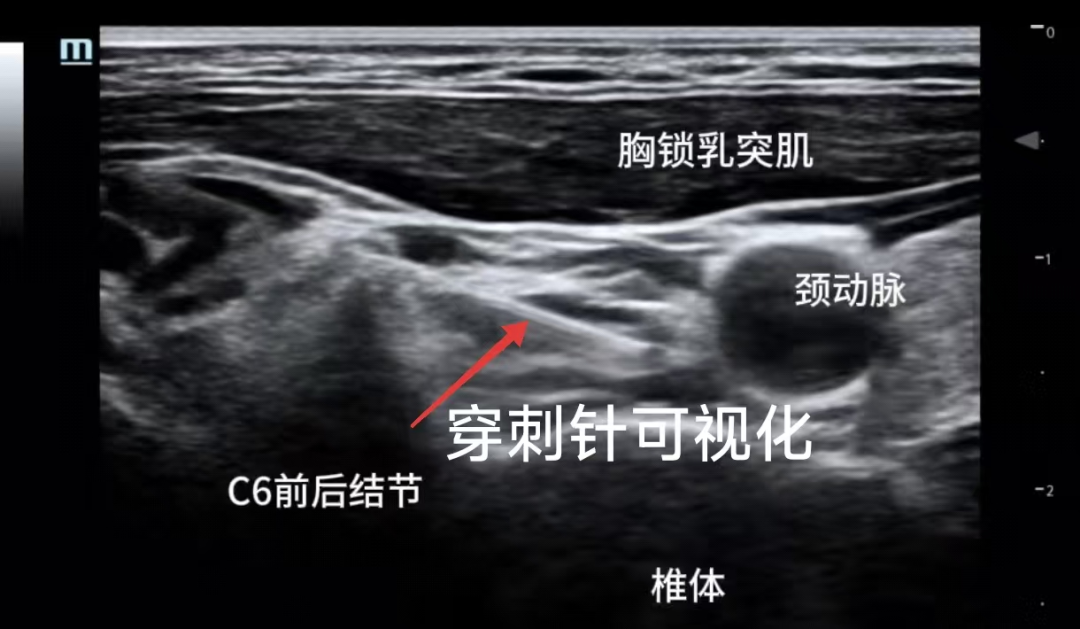

疼痛门诊采用的超声可视化星状神经节阻滞技术与传统盲探穿刺方法相比,实现了超声引导可视化操作。

医生能够实时观察穿刺针的位置和药液扩散情况,精准地将药物送达目标区域,同时有效避开血管、神经等重要结构,减少了并发症风险,为患者提供了更加安全有效的治疗选择。